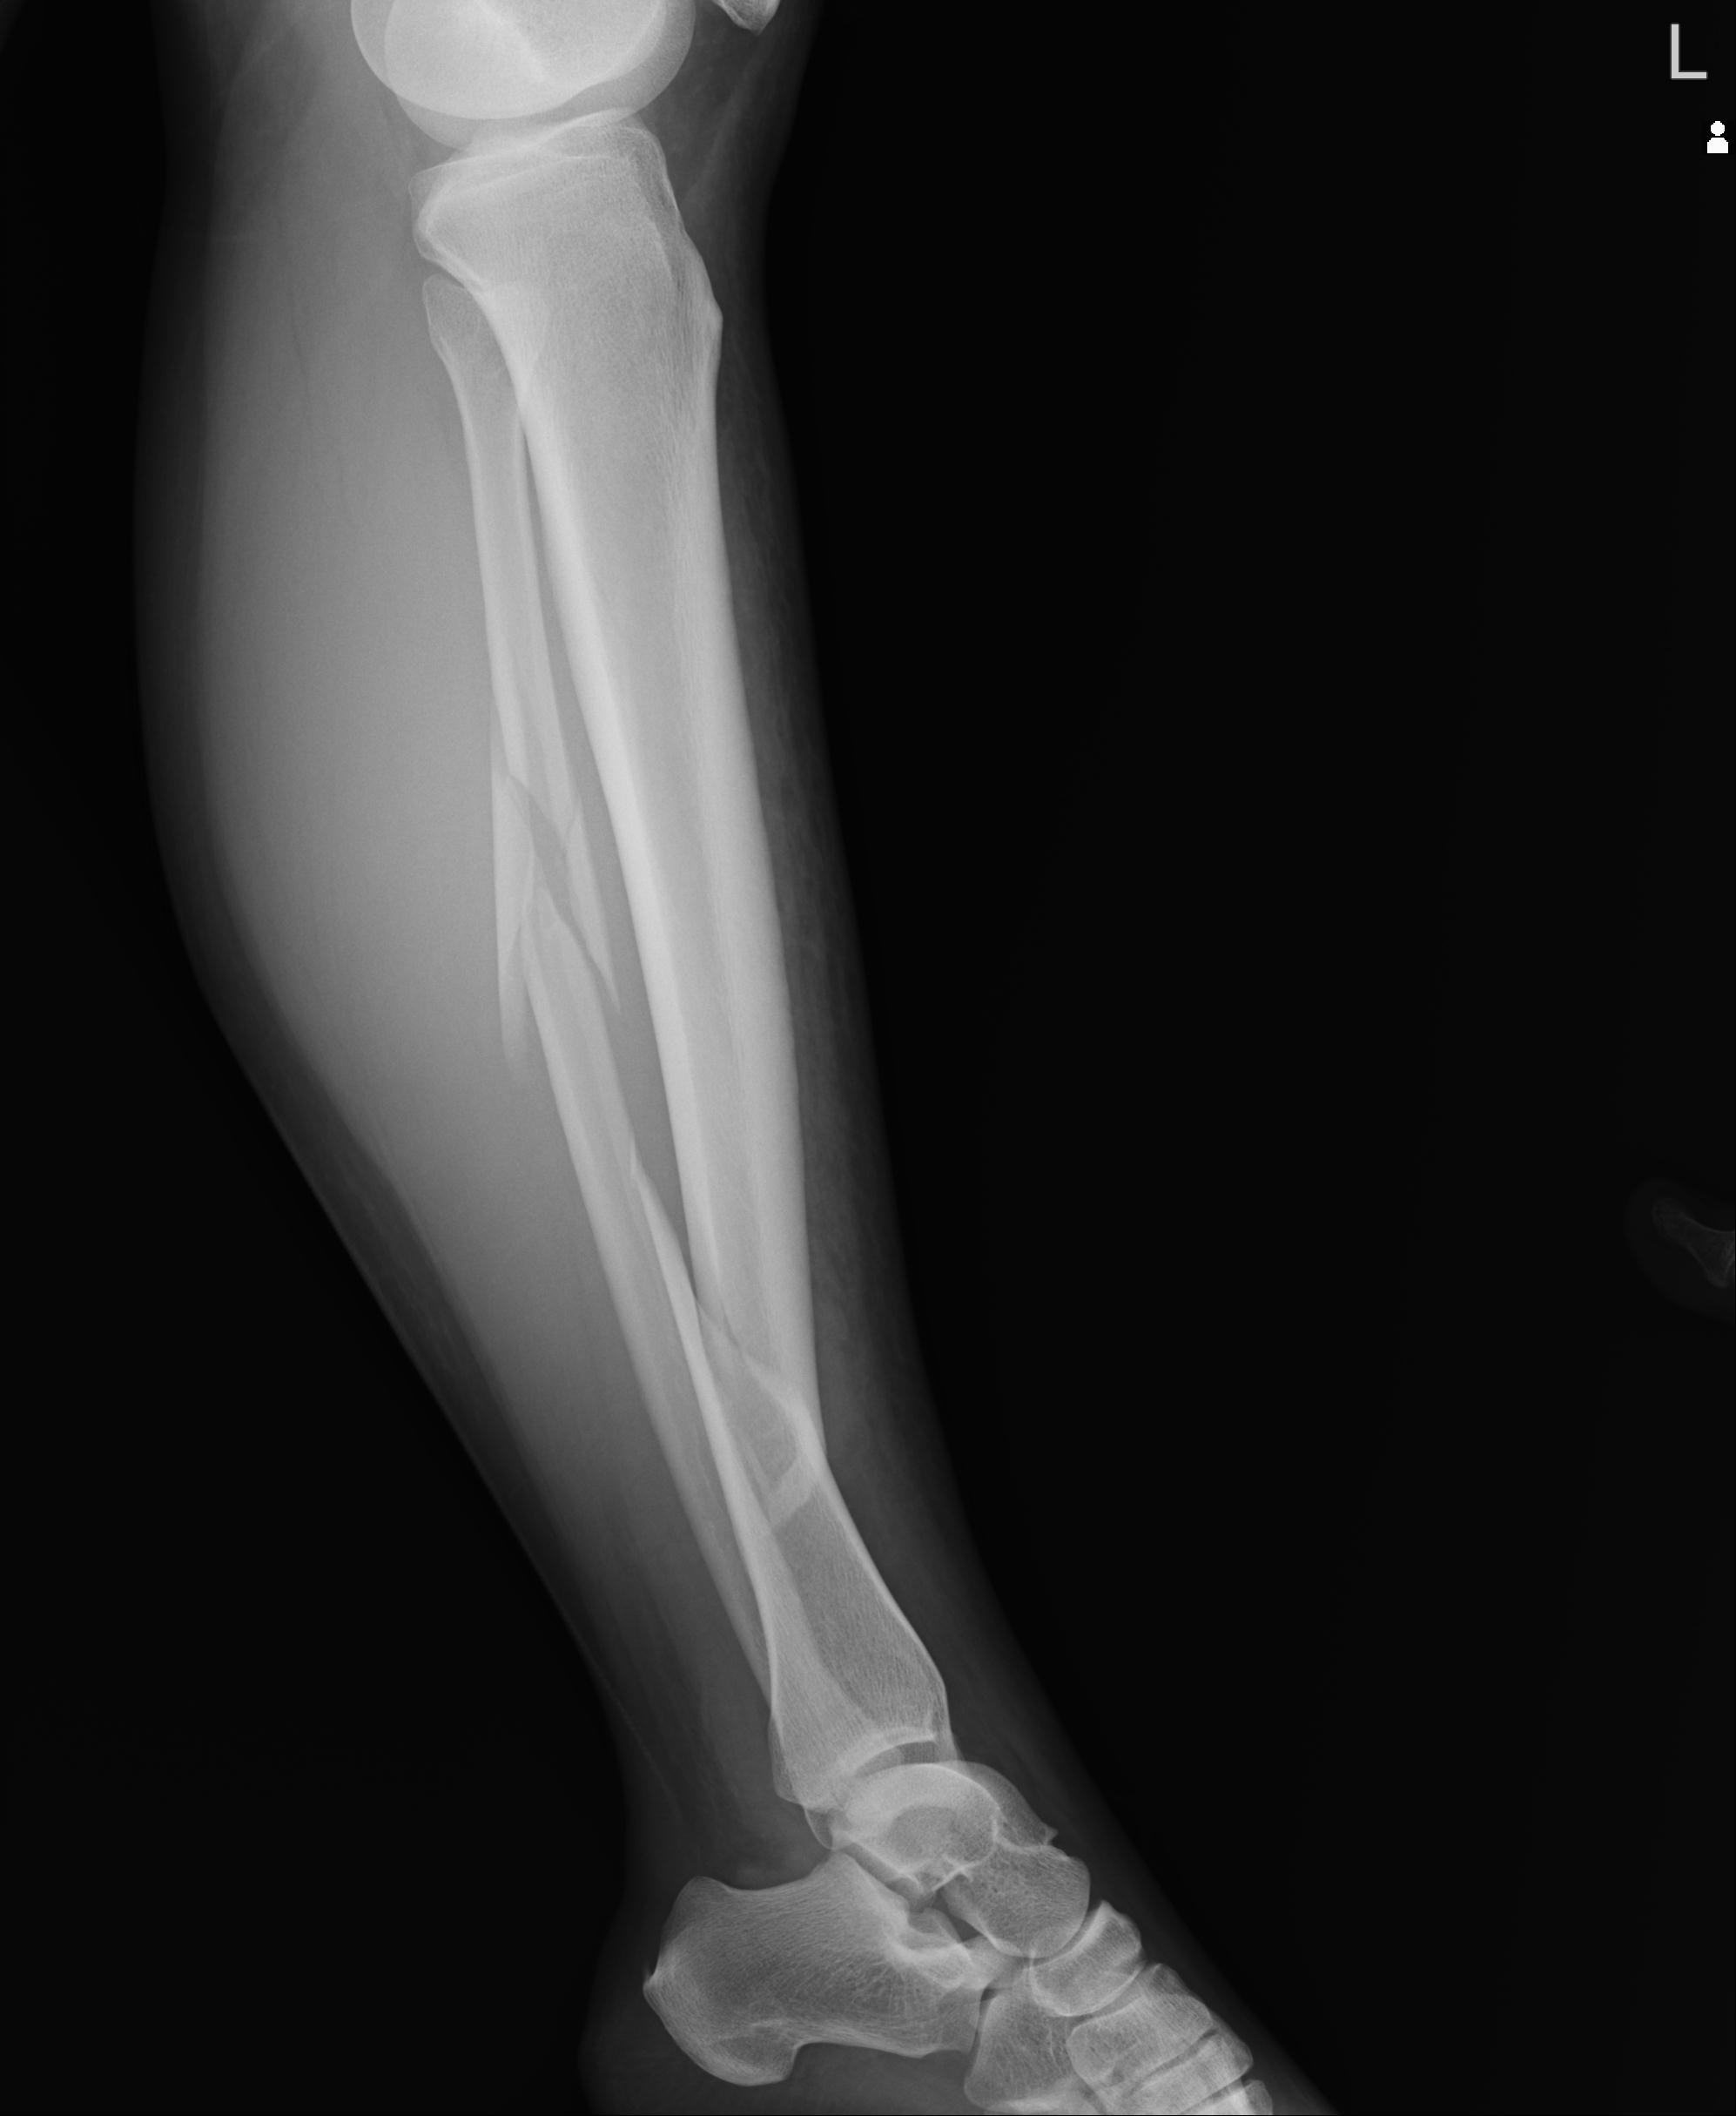

102803 1/12(キウスなし) 1/27 左下腿 4R 30歳女性 左脛骨軸内釘